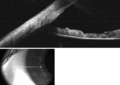

طريقة نسبة EZ هي إحدى الطرق لحساب عمق الغرفة الأمامية المقدر.[2] للبدء ، ينظر المريض إلى هدف على مسافة مع تغطية عين واحدة. يلتقط الفاحص صورة رقمية للعين المفتوحة المفحوصة ، من الجانب ، بشكل عمودي على المحور البصري (صورة الملف الشخصي). .

يجب بعد ذلك قياس المتثابتات التالية في الصورة ، باستخدام حاسوب شخصي أو هاتف ذكي (الأشكال 1،2):

1. مسافة البكسل بين الحوف (ملتقى القرنية الصافية والصلبة البيضاء) ومقدمة القرنية . يشار إلى هذه المسافة باسم Z.

2. مسافة البكسل بين الحوف ومركز الحدقة . يشار إلى هذه المسافة باسم E.

نسبة E: Z هي النسبة الحسابية بين E و Z.

ترتبط هذه النسبة خطيًا بعمق الغرفة الأمامية بالمعادلة التالية:

عمق الغرفة الأمامية (معبراً عنه بالمليمترات) = -3.3 × نسبة EZ + 4.2

وقد ثبت أن هذا التقدير دقيق مع مدي ثقة 95٪ +/- 0.33   مم خطأ ، بالمقارنة مع قياسات عمق الغرفة الأمامية بواسطة تصوير شيمبفلنج .[2]

شكل 1. حساب نسبة EZ.

الشكل 2. أعماق مختلفة للغرفة الأمامية كما تُرى من العرض الجانبي العمودي (الجانبي) كلما كانت الحدقة أماميًا ، كانت الغرفة الأمامية أقل عمقًا. في الصورة الموجودة في أقصى اليسار ، تكون الحدقة خلفية نسبيًا (يتراجع) ، مما يشير إلى نسبة EZ أقل من 0.5 والحجرة الأمامية أعمق من 2.5 مم. في الصورة الوسطى ، تكون الحدقة في منتصف الطريق بين الصلبة الخلفية والقرنية من الأمام ، مما يشير إلى نسبة EZ تبلغ 0.5 ، وعمق غرفة متوسط يبلغ حوالي 2.5 ملم. في الصورة الموجودة في أقصى اليمين ، تكون الحدقة أمامية جدًا (أماميًا) ، مما يشير إلى أن نسبة EZ تزيد عن 0.5 وأن الغرفة الأمامية الضحلة أقل من 2.5 مم.